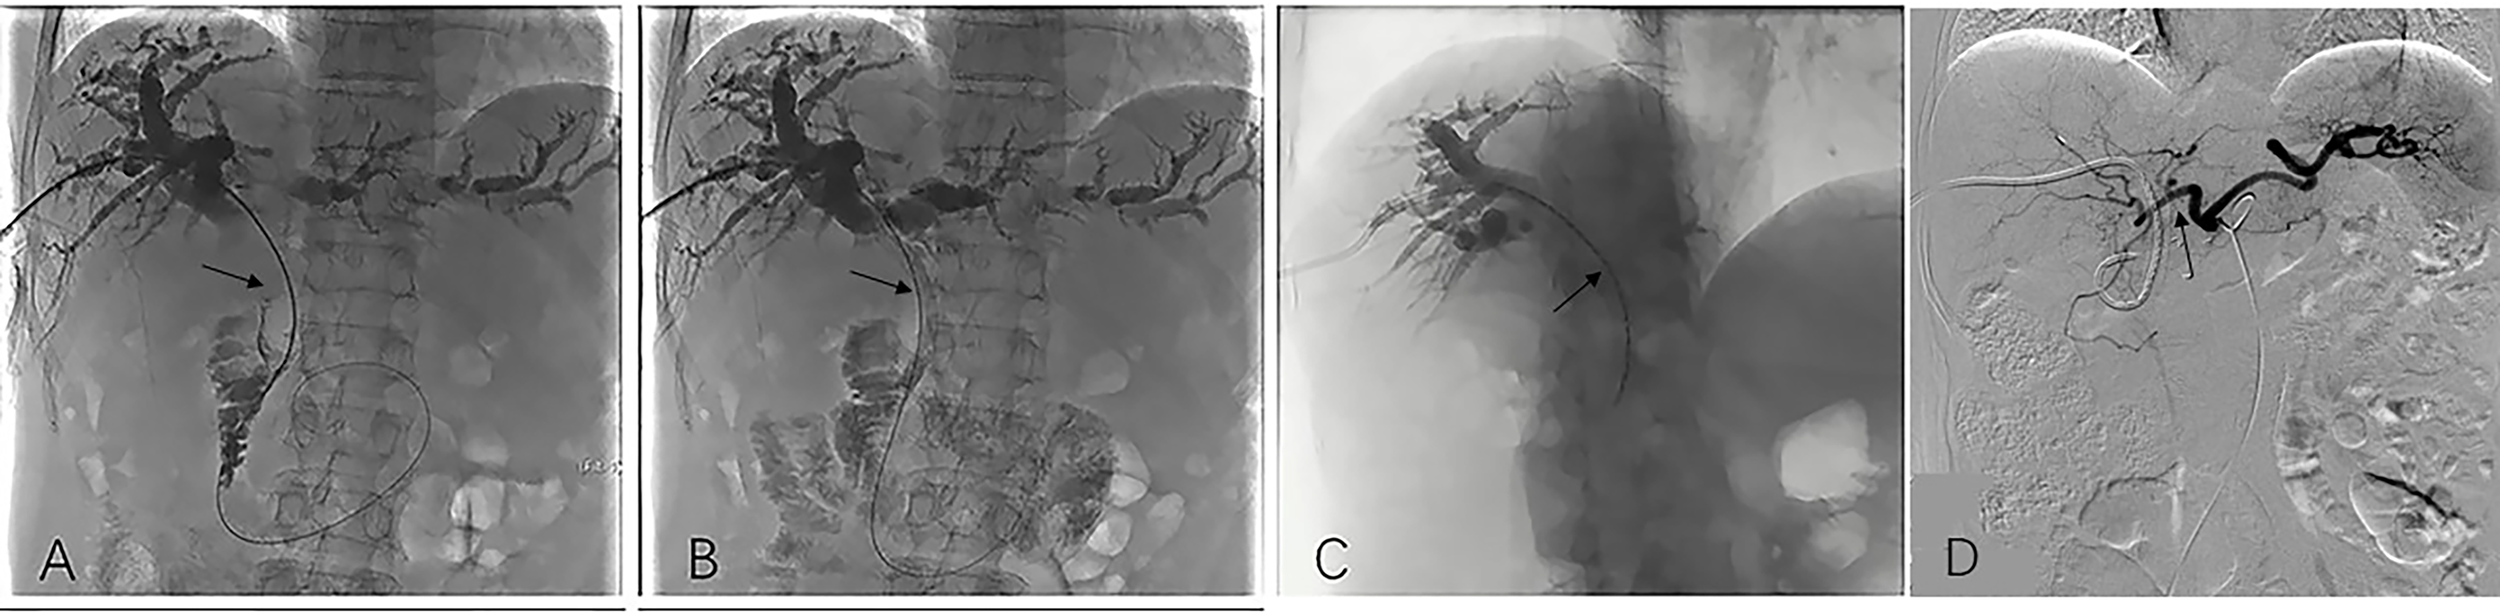

Cholangiography was employed to ascertain the extent of the stent. A 0.035-inch exchange guidewire was introduced at the point of entry into either the duodenum or the distal end of the common bile duct. Subsequently, utilizing an elongated sheath, the stent system was inserted in such a manner that the designated markers at both termini were positioned at a minimum distance of one centimeter above the obstructed segment, after which the stent was released (Figures 2A, B). To validate the efficacy, cholangiography was once again employed.

Figure 2

Image dates image showed the operation procedure of biliary stenting with iodine-125 seed strand placed in the obstructed segment of the bile duct. Imaging under donor-specific antibody (DSA) showed a bile duct tumor thrombus and a filling defect inside the bile duct (black arrow) (A); DSA imaging showed biliary stenting were placed in the obstructed segment from the hilar region to the distal common bile (black arrow). Subsequently bile duct drainage restored to open and the bile duct filling defect is disappeared (B). DSA Imaging showed iodine-125 radioactive seed strips were placed through the PTCD tube (black arrow) (C); After the total serum bilirubin decreased to normal and the liver function of the patient recovered, HAIC was conducted (black arrow) (D). HAIC, hepatic artery infusion; PTCD, percutaneous transhepatic cholangial drainage.

Iodine-125 seed strand implantation

The administration of the iodine-125 seed strand into the biliary tract was performed via an 8F biliary drainage tube. Subsequently, the seed strand and drainage tube were connected using a 3-way tube to enable continued bile drainage. Following the release of the stent, the seed strand was promptly positioned within the stenosis segment. As the guidewire was retracted, the seed strand was released in the bile duct, facilitating the irradiation of the seeds onto the obstruction (Figure 2C).

HAIC

The HAIC procedure was performed by experienced physicians following the implantation of biliary stenting with iodine-125 seed strand. This was done at a three-week interval. The modified Seldinger’s technique was employed after preparing the skin and administering local anesthesia, whereby the right femoral artery was punctured using a vascular sheath. The catheter was placed in the common hepatic artery, which served as the target artery for perfusion chemotherapy (Figure 2D). Chemotherapy agent was infused through the microcatheter as follows: gemcitabine is administered over 30 minutes at a dose of 600-1000 mg/m2, and oxaliplatin is administered over 2 hours at a dose of 60-100 mg/m2.